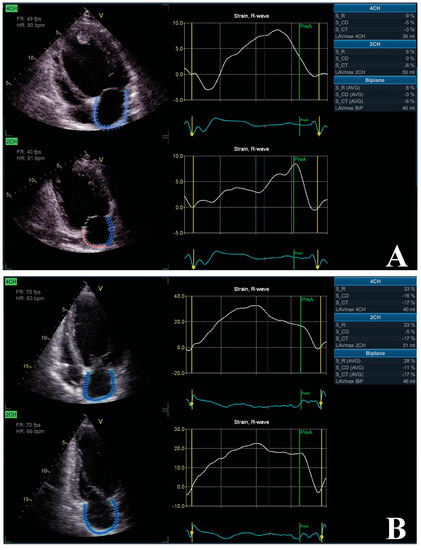

- Feneon, D.; Behaghel, A.; Bernard, A.; Fournet, M.; Mabo, P.; Daubert, J.-C.; Leclercq, C.; Donal, E. Left atrial function, a new predictor of response to cardiac resynchronization therapy? Heart Rhythm 2015, 12, 1800–1806. [Google Scholar] [CrossRef]

- Valzania, C.; Gadler, F.; Boriani, G.; Rapezzi, C.; Eriksson, M.J. Effect of Cardiac Resynchronization Therapy on Left Atrial Size and Function as Expressed by Speckle Tracking 2-Dimensional Strain. Am. J. Cardiol. 2016, 118, 237–243. [Google Scholar] [CrossRef]

| Feneon et al. | [86] | 2015 | 79 | LAS-r LA pre-ejection index | 6 Mo to evaluate the impact of CRT on LA strain | LAS-r was a good predictor for CRT responsiveness, regardless of cardiac pathology |

| Valzania et al. | [87] | 2016 | 30 | LAS-r | 12 Mo for the impact of CRT on LA strain and the relationship with some parameters | CRT responsiveness had beneficial impact on LA size and LAS-r. LV function, filling pressures, and mitral regurgitation significantly influenced LA remodeling |

| Badran et al. | [79] | 2017 | 37 | LAVmax LAVmin LAVpre-A; LATF LAS-r; LAS-cd | 3 Mo for evaluating LA remodeling | LAVmax, LAVmin, LAS-r, LAS-cd, LATF were significantly improved in those who were responders to CRT |

| Dokuni et al. | [85] | 2020 | 90 | LAS-r LAPF | 6 Mo for the role of CRT on LA strain function | CRT reduced LA dyssynchrony, which in turn improved LAS-r and LAPF |